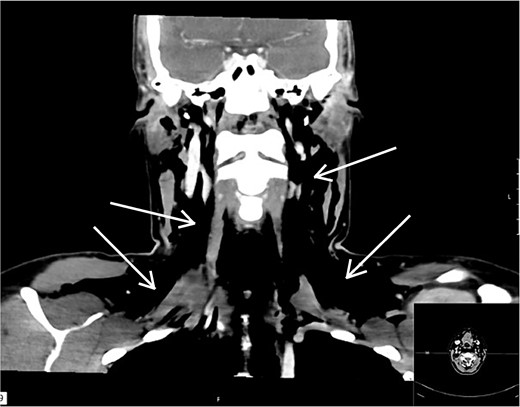

The surgery was performed without any difficulties and diathermy was used for electrocoagulation, and Ligasure was used for tissue sealing. Hemostatic material, Cellistypt®, was placed on both sides of the trachea after the thyroid was removed. No drain was inserted. She was discharged home in good condition without any complications. Carbimazole was discontinued, and the patient started on 100 mcg of levothyroxine daily. The patient was on a routine 2-week sick leave from work. The postoperative course was uneventful until the night of Day 10, when the patient experienced nocturnal coughing bouts followed by throat pain, voice changes, and a sensation of throat fullness. Upon examination at the doctor's office the following day, swelling was observed laterally on the neck bilaterally, most pronounced on the left side from upper thorax to the temple. The patient reported that the swelling had increased since the past hours. She reported increasing pain in the jaw/neck area and noted bubbling and crackling sensations in the throat. She was taken immediately to the hospital due to a threatened airway. The surgical incision appeared unremarkable without any signs of infections. A CT scan was performed revealing extensive subcutaneous emphysema, including pneumomediastinum and pneumopericardium without any defect in the trachea or oesophagus (Fig. 1). We consulted with the national hospital and were advised to only insert a drain and not to search for possible damage to the trachea, as this could cause more harm and the hole may have already begun to close. When the incision was opened under general anesthesia, air immediately escaped, and a drain was placed into the wound cavity without any search for a defect. The skin was closed tightly around the drain to prevent air leakage and displacement. The drain was connected to active suction at −8 mm Hg which was gradually reduced until −1 mm Hg on Day 9 and removed on Day 11 (Fig. 2). She was administered broad-spectrum antibiotics according to Norwegian guidelines and awoken the day after drain placement and discharged on Day 11. At the follow-up 16 days later, she described some discomfort in her throat, feeling dry, and sore but elsewhere she was in good health, and all emphysema had been absorbed. She had returned to full-time work.